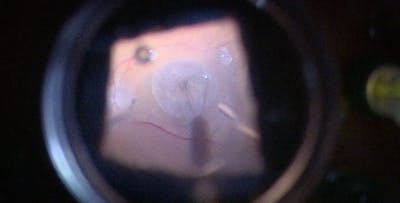

The RETINAWS panel led by Kourous Rezaei, MD, discuss techniques for vitreoretinal surgery and rare surgical cases.